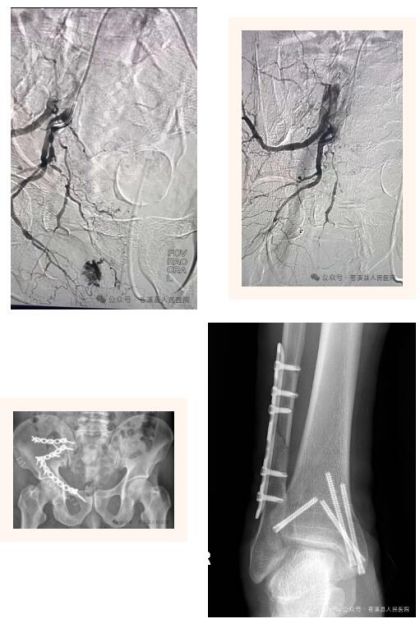

介入拴塞治疗,“堵”住出血口

经与家属沟通,介入科团队通过“米粒”大小的创面经股动脉穿刺,进入出血病灶处,进行精准栓塞。术后患者破裂处出血征象消失,血压、心率逐步恢复正常,仅在重症监护室观察一天就转入了骨一科普通病房。经过充分准备后,择期进行了骨盆骨折、右踝骨折手术治疗。 目前,患者的各项指标均恢复正常,病情稳定,正在康复治疗。